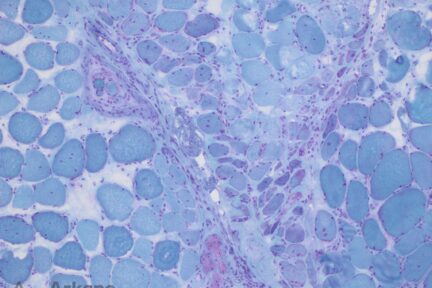

Perifascicular Atrophy in Dermatomyositis

Perifascicular Atrophy in DermatomyositisThis case shows an acquired inflammatory myopathy with well-developed perifascicular atrophy. Generally speaking, acquired inflammatory myopathies may…